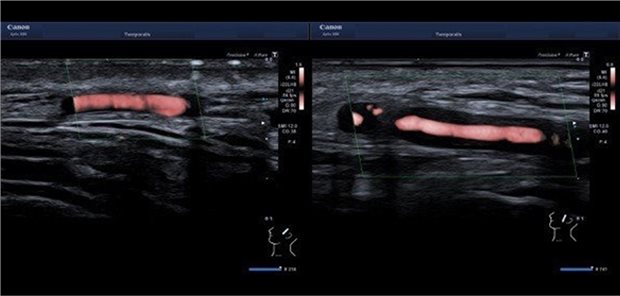

Fragen nach Sehstörungen, Kopf- und Kauschmerzen und eine rasche Ultraschalluntersuchung können entscheidend sein, um Patienten mit Riesenzellarteriitis vor der Erblindung zu bewahren.

Ein Fallbeispiel macht deutlich, wie bei Patienten mit seit Kurzem bestehenden Arthralgien, Antikörpern gegen CCPA und im Powerdoppler-Ultraschall nachweisbarer Synovitis vorzugehen ist – Studien stützen das Ergebnis.